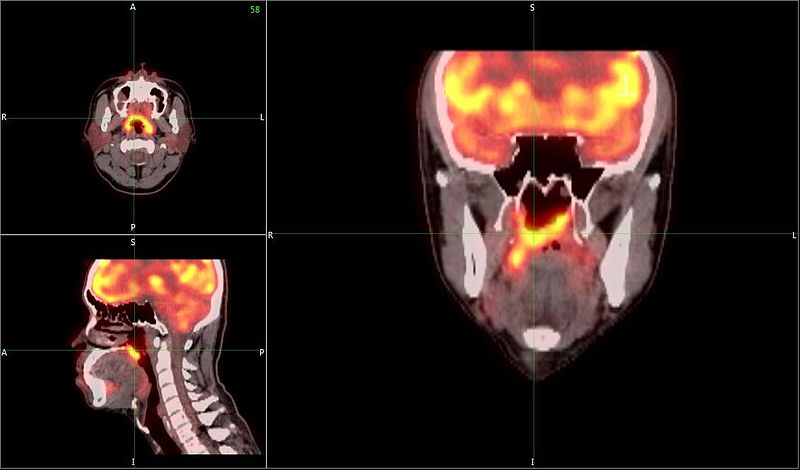

Doctors and patients alike rely on medical imaging – Magnetic Resonance Imaging (MRI), Computed Tomography (CT), and Positron Emission Tomography (PET) – for accurate diagnosis and treatment of a variety of conditions. These technologies are particularly important for patients who have, and for researchers who investigate, neurodegenerative conditions like Alzheimer’s and Parkinson’s.

These scans generate massive datasets – tens to even hundreds of thousands of images – for each subject, and in a research context, studies often include hundreds of subjects, which makes quality assurance (QA) an important, if daunting, part of the medical imaging process. Importantly, QA requires the use of appropriate quality control (QC) methods in order to identify – ideally, “in the moment” – data in need of post-processing correction or reacquisition. Imaging is costly, and many projects (and patients!) lack the funds to reacquire images if Quality Control issues are detected after the acquisition period.